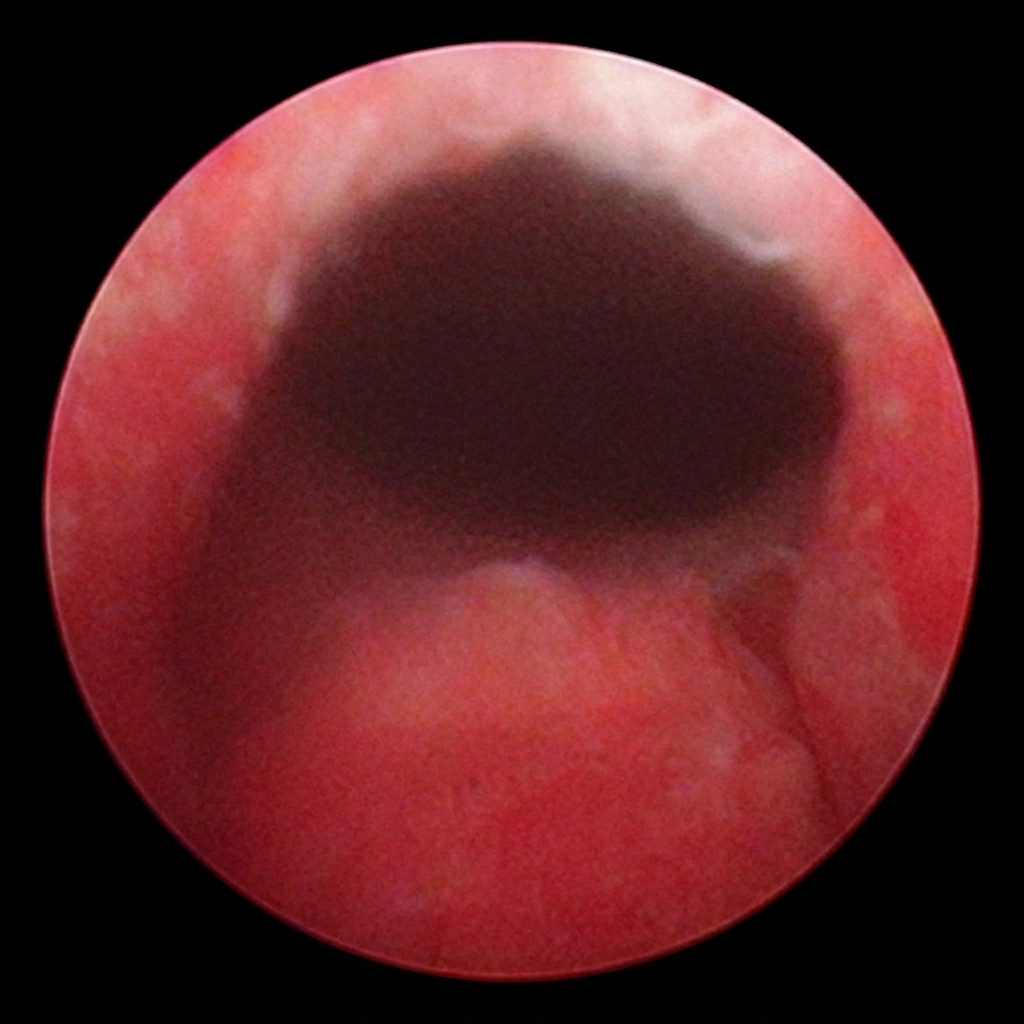

유로리프트 시술과정

ZAII UROLOGY HOSPITAL